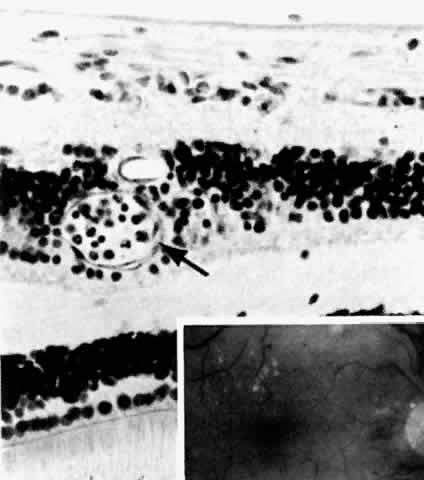

The earliest manifestation of diabetic retinopathy is the appearance of microaneurysms (Fig. 5, Color Fig. D). They appear as small red dots clinically and often are seen more readily on fluorescein angiography, where they fill and leak, with staining of the vessel wall.35 Histologically they are small “outpouchings” of the capillary vessel wall and are usually saccular but occasionally fusiform in shape. They can occur anywhere along the capillary network between the arteriole and venule.18 Some microaneurysms, however, do not fill with fluorescein and have been shown to be thin-walled capillary outpouchings filled with erythrocytes. They may represent either one stage of microaneurysm formation or a specific type of it.36

Fig. 5. Retinal capillary microaneurysm (arrow) is characterized by its thin wall and location in the capillary area of the retina (middle retinal layers) rather than the major vessel area (inner retinal layers). Inset. Fundus appearance of microaneurysms and hard or waxy exudates. (Main figure, H&E, × 176)

As shown by trypsin digestion, capillary pericytes are lost first,27 followed by endothelial cells (Figs. 6 and 7). Aldose reductase, one of the enzymes in the sorbitol metabolic pathway, is present in significant quantities in retinal capillary pericytes, but not in endothelial cells, and may thus be implicated in the formation of microaneurysms.37 The final result is an acellular segment of capillary that is nonperfused on fluorescein angiography.36

Fig. 6. Diabetic retinal capillary. A. Basement membrane shell (arrows) is the only remaining indication of where the pericytes had been. B. Nondiabetic normal capillary shows the basement membrane shell (arrow) around the pericyte. C. Diabetic capillary has only a basement membrane shell (arrow), with the nucleus absent. (A, PAS, × 630; B, PAS, × 850; C, PAS, × 630)